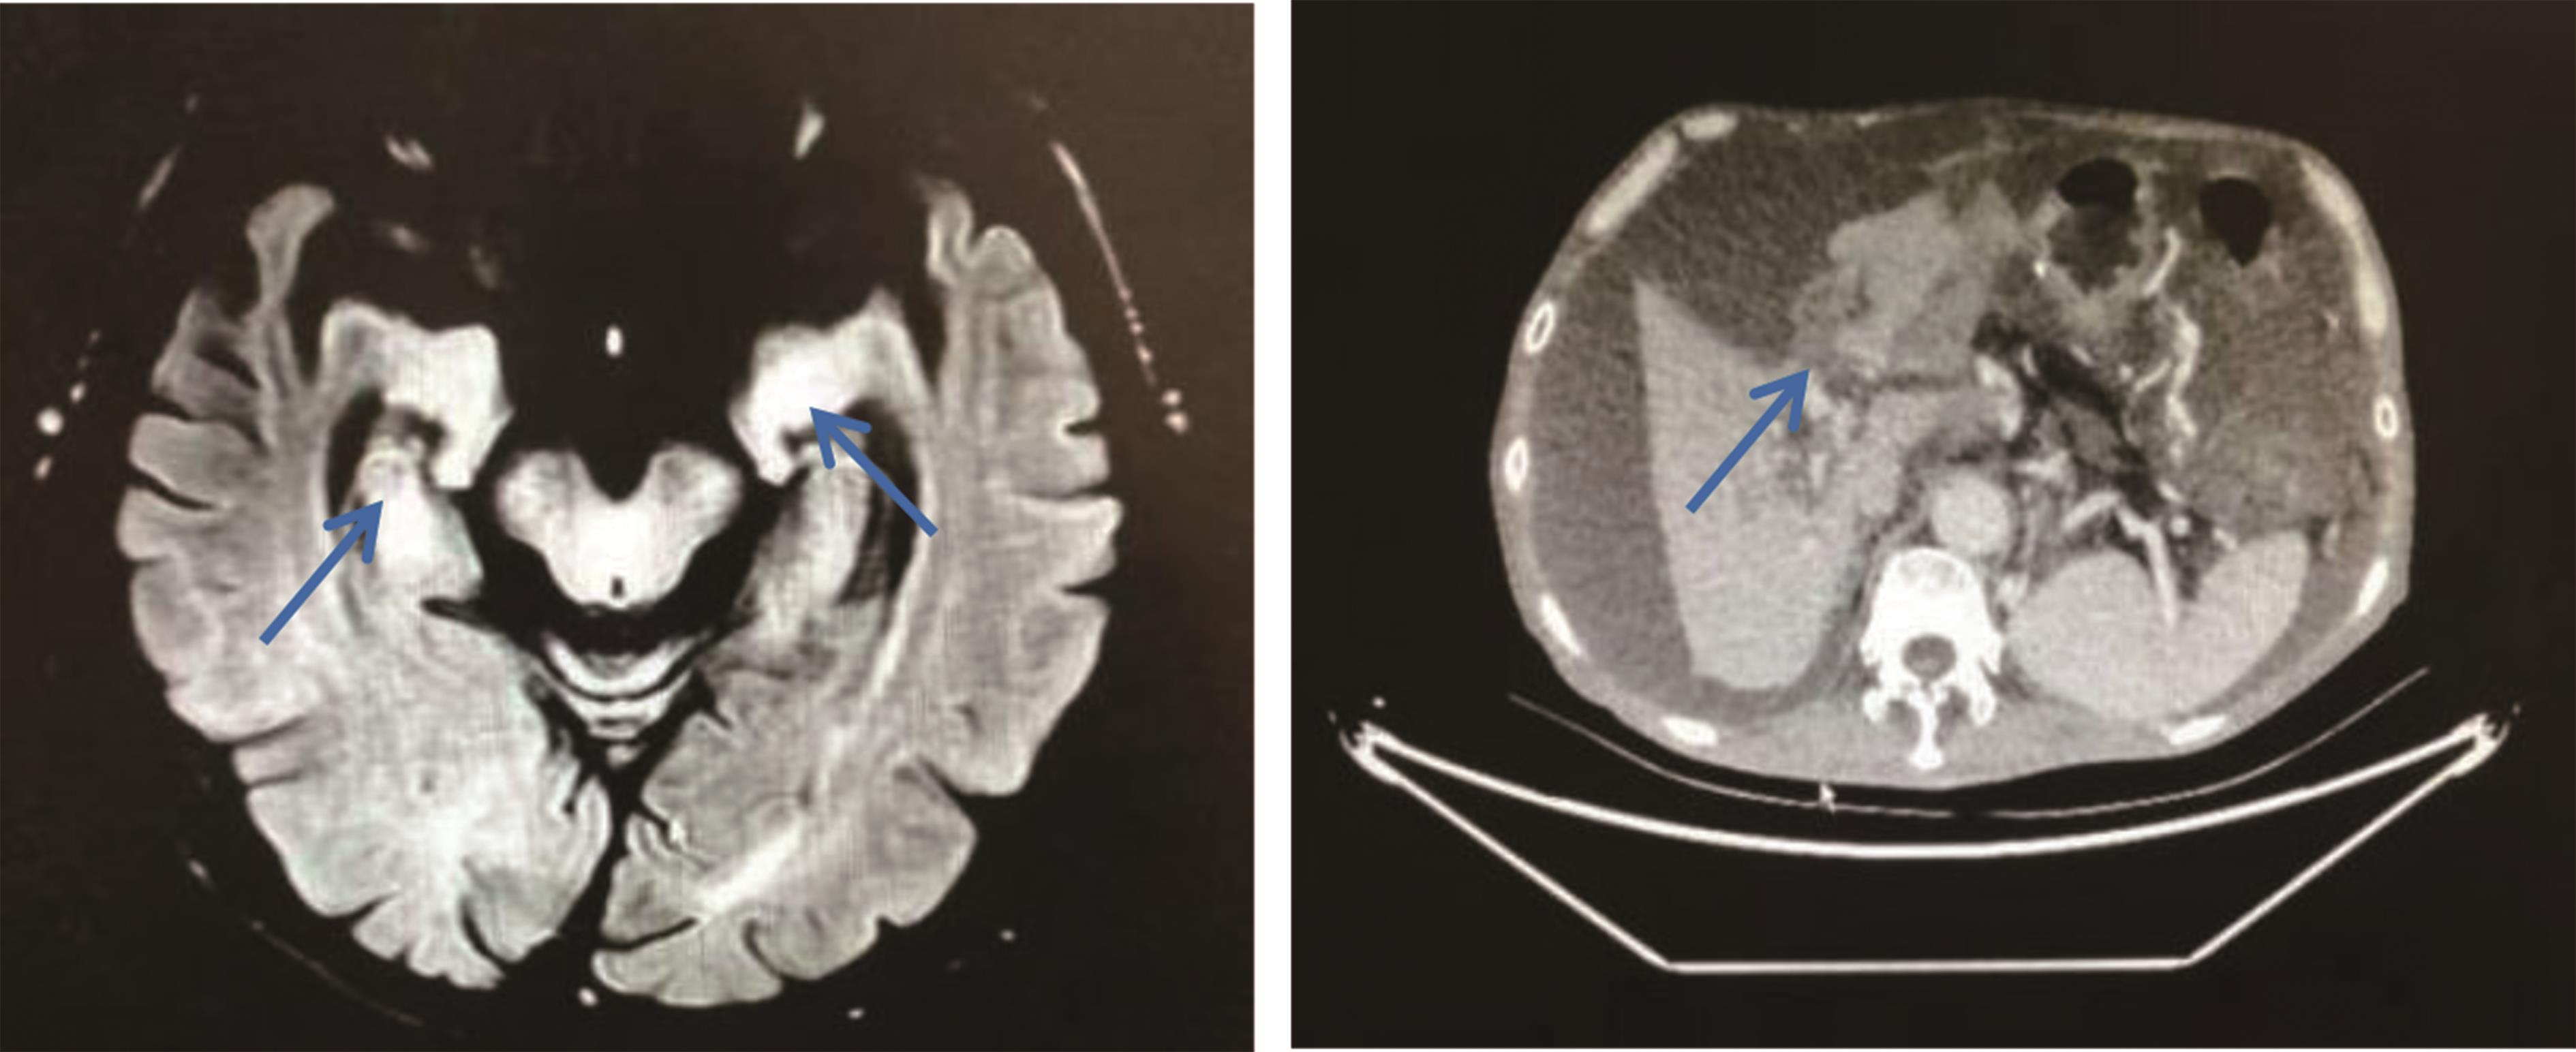

• 胰腺癌合并抗AMPA2受体脑炎1例

2023, 48(6):735-737. DOI: 10.13406/j.cnki.cyxb.003244

摘要 (43) HTML (17) PDF 2.65 M (174) 评论 (0) 收藏

摘要:

• 0+1

• 1+1

• 2+1

• 3+1

• 4+1